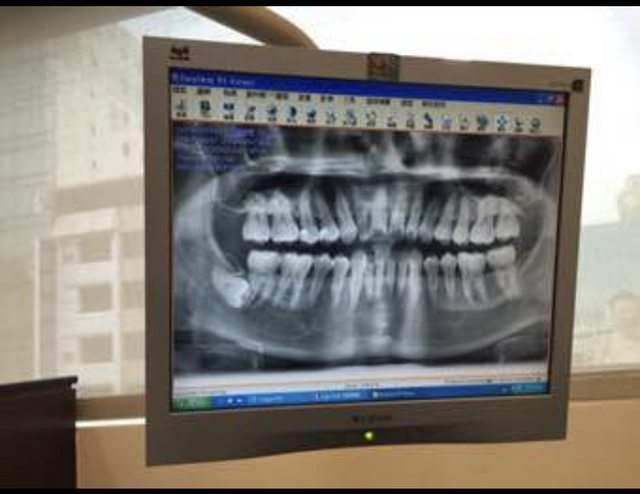

去看醫生照X光他傻眼

https://i.imgur.com/82aIEpj.jpg

他說你的旁邊有一顆完整成長

橫躺的智齒噎

你都不會痛嗎

我說完全沒有感覺